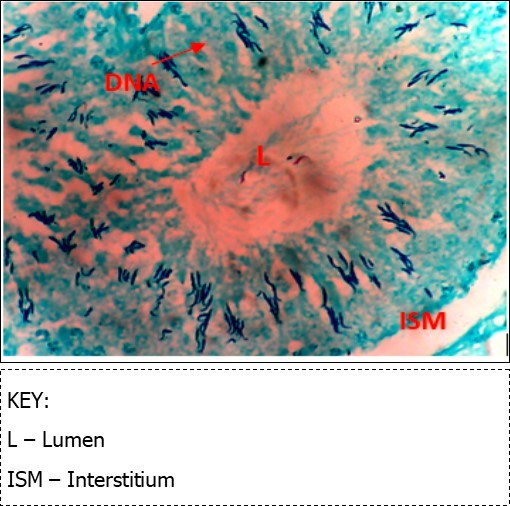

Figure 7.(DC+1000mg/kg.bw of AP) X400 – Section of testis showing scanty DNA deeply stained with magenta color. DNA strands has reduced clusters

Figure 8.(DC+Metformin) X400 – Section of testis showing deeply stained DNA with magenta color. DNA strands are higher clusters.

From findings in this study, irregular and distorted arrangements of DNA in all diabetic groups (Groups B, C, D, E and F) when compared with the normal control group, may have been due to displacement of sertoli cell within the germinal epithelium of seminiferous tubules. Strands of DNA were also seen arrange in clusters in diabetic groups, showing altered and defective structure which might have resulted from base free side deletion, frame shift, cross-linking and chromosomal rearrangement. The intensity of magenta colour development in Feulgen reaction for DNA demonstration was proportional to DNA concentration. There was reduced colour intensity in all diabetic groups (Groups B, C, D, E and F) when compared with the normal control. This is in line with report from Aitken and Krausz (2001). However the degree of distortion and cross-linking of DNA strand in the group of diabetic animal models placed on high dose (1000mg/kg.bw) of A. polytricha which may be a sign of amelioration. Groups C, D and F placed on 250mg/kg.bw A. polytricha, 500mg/kg.bw A. polytricha and standard anti-diabetic drug (metformin) respectively did not show remarkable differences in terms of DNA arrangements when compared with the diabetic control group. Groups D (500mg/kg.bw A. polytricha) and group E (1000mg/kg.bw) showed visible improvement in magenta colour intensity when compared with the diabetic control group.

The marginal reversal of DNA damage following 21 days of A. polytricha administration, as observed in this study may be linked to its polysaccharides constituent found to exhibit antimutagenic effect against in-vivo DNA damaging activities of indirectly acting alkylating agent. A. polytricha may have improved antioxidant status of experimental animals and was capable of ameliorating DNA damage which may be attributed to its potentials to regulate concentration of carboxymethyllysine (CML) and advanced glycation end (AGE) which are important triggers of oxidative stress in the reproductive tract of diabetic animals. AP is known to be a good exogenous source of antioxidant and may have ameliorated further DNA damage.